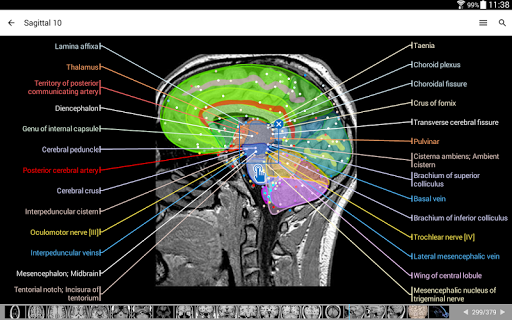

- وحدتان جديدتان: الدماغ - TOF والأوعية الدموية الدماغية ، أطلس التشريح الوعائي العصبي الطبيعي لشرايين الدماغ على الأوعية الدموية الدماغية. - تم إعادة صياغة الواجهة. - تتوفر علامة تبويب جديدة باسم "QuickLinks" ، ترسل وحدات في أقسام من جسم الإنسان وتسمح لك بالسفر السريع إلى الوحدات التي تبحث عنها. الخلل الصغيرة الثابتة.